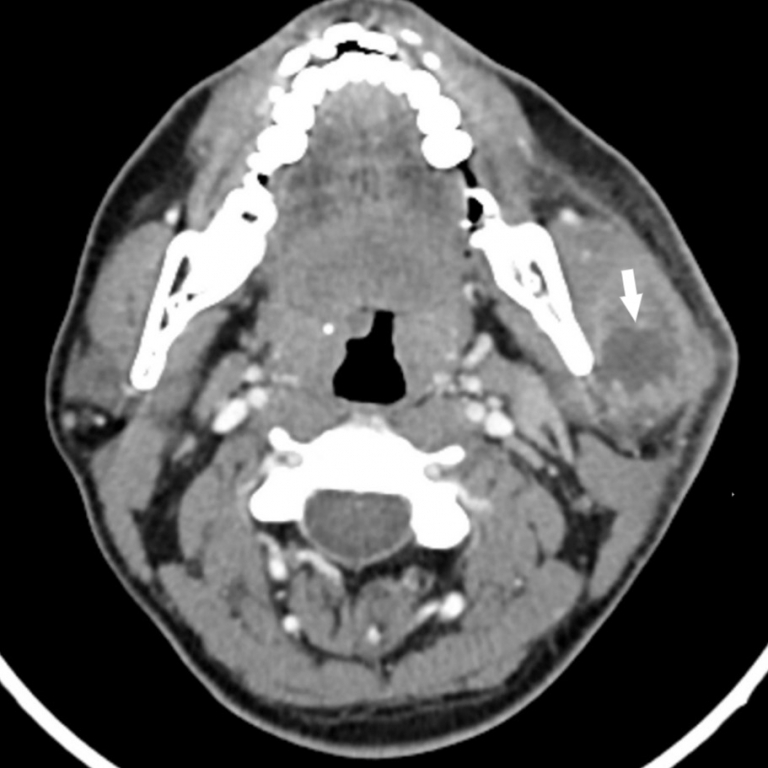

Parotid gland pathologies are clinically significant due to potential involvement of the facial nerve. The facial nerve may be affected by infectious pathologies, trauma, tumors, and iatrogenic causes. Parotid abscesses, which frequently develop in the presence of conditions such as poor oral hygiene, immunosuppression, dehydration, and sialolithiasis, require careful management for this reason. This article presents the case of a 30-year-old immunocompetent male patient with a parotid abscess secondary to blunt trauma. This case is unique in the literature both due to its development following blunt trauma and the isolation of Kocuria kristinae in culture.